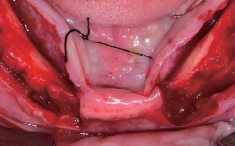

판막 거상

식립 부위 천공

절개(Releasing incision)

Membrane holding suture

봉합